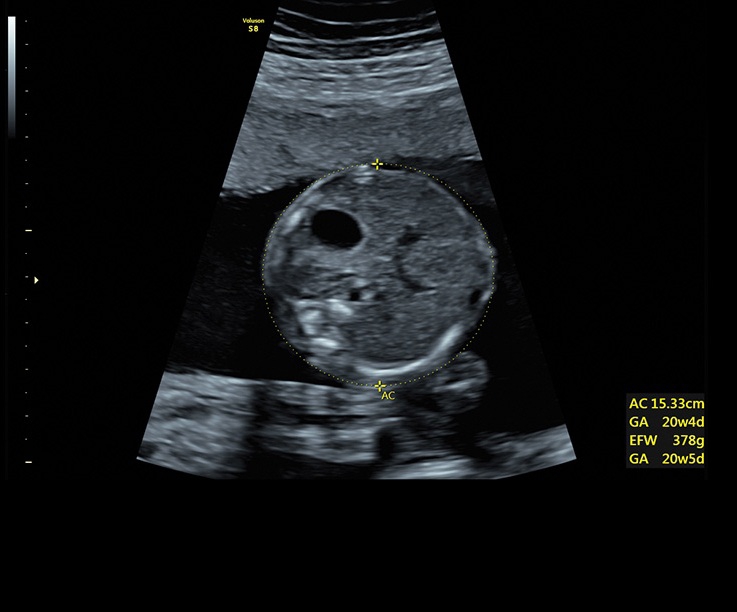

Ультразвуковая платформа Voluson S8 представляет собой оборудование экспертного класса с передовыми возможностями и высоким уровнем автоматизации процессов. Она позволяет проводить сканирование в режимах 2D, 3D и 4D с высоким качеством изображений.

Аппарат Voluson S8 базируется на надежной платформе VCA, которая имеет множество положительных отзывов. Она обладает высококонтрастной технологией объемной реконструкции, обеспечивая качественное воспроизведение изображений. Информация выводится на широкоформатный цветной монитор размером 23 дюйма для убедительной демонстрации плода будущим родителям и облегчения работы врача.

• Технология автоматической фетометрии в 2D режиме (SonoBiometry): Эта технология позволяет автоматически измерять бипариетальный размер, окружность головы, окружность живота, длину бедра и плеча плода, обеспечивая точные и надежные измерения.

• Высокое качество изображений: Voluson S8 обеспечивает высококачественные изображения, позволяющие детально оценить состояние плода и обнаружить возможные патологии.

• Сложные инструменты для оценки качества плода: Сканер оснащен инновационными инструментами, позволяющими проводить детальную оценку состояния плода, включая его сердечную деятельность, анатомию и кровоток.